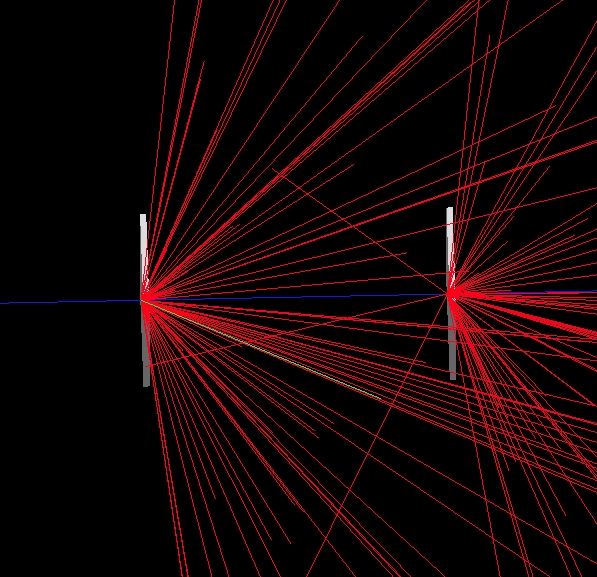

Οι ειδικοί χρησιμοποιούν ακτινοβολία περισσότερο από έναν αιώνα για τη θεραπεία του καρκίνου – και αυτό διότι οι ακτίνες καταστρέφουν το DNA των καρκινικών κυττάρων.

Το σωματίδιο της ακτινοβολίας α (ο πυρήνας του στοιχείου ηλίου) είναι βαρύ και μεγάλο διότι αποτελείται από δύο πρωτόνια και δύο νετρόνια. Είναι περίπου 7.000 φορές μεγαλύτερο από το σωματίδιο της ακτινοβολίας β (ηλεκτρόνιο) ή από τα κύματα της ακτινοβολίας γ.

Για τον λόγο αυτό, όπως εξήγησε στο BBC ο επικεφαλής της δοκιμής δρ Κρις Πάρκερ, «η ακτινοβολία α είναι πιο καταστρεπτική από τις υπόλοιπες. Χρειάζονται μόλις δύο ή τρία ‘χτυπήματα’ του καρκινικού κυττάρου προκειμένου αυτό να καταστραφεί σε σύγκριση με χιλιάδες ‘χτυπήματα’ ακτινοβολίας β που είναι απαραίτητα για την εξόντωση του καρκίνου».

Συγχρόνως τα σωματίδια α προκαλούν πολύ μικρότερες βλάβες στον υγιή ιστό που περιβάλλει τον καρκινικό. «Εχουν μικρό εύρος, λίγων μόνο εκατομμυριοστών του μέτρου. Ετσι μπορούμε να είμαστε σίγουροι ότι προκαλούμε βλάβη μόνο στα σημεία που εμείς επιθυμούμε» συμπλήρωσε ο δρ Πάρκερ μιλώντας στο βρετανικό ειδησεογραφικό πρακτορείο.